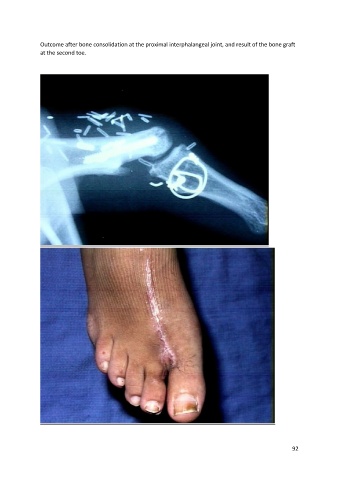

Outcome after bone consolidation at the proximal interphalangeal joint, and result of the bone graft

at the second toe.